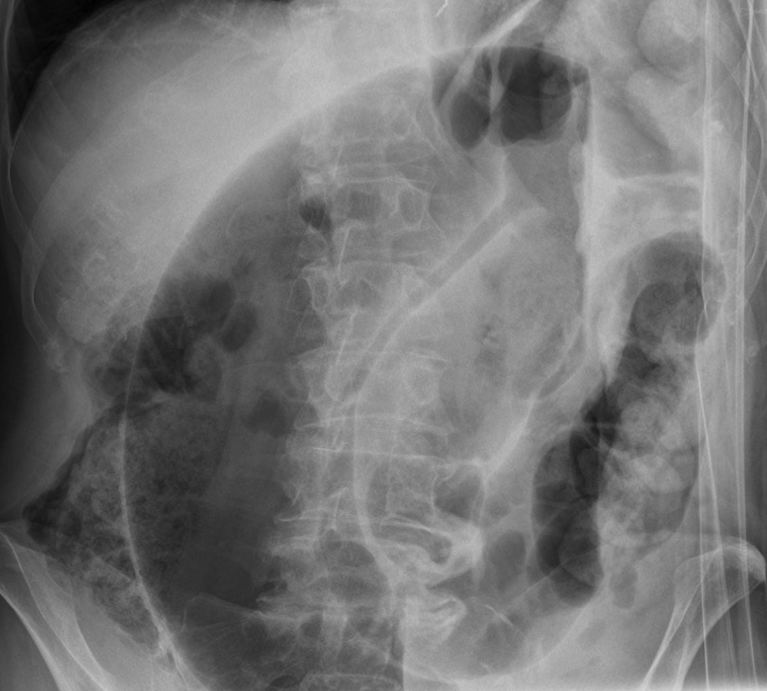

What is shown in the image?

AXR showing the classic ‘coffee bean sign’, as seen in sigmoid volvulus.

Some centres will perform an abdominal radiograph (AXR). This will classically show (in around 60-75% cases) a “coffee-bean sign” arising from the left iliac fossa; if the ileocaecal valve is incompetent, the AXR will also show signs of small bowel dilatation.